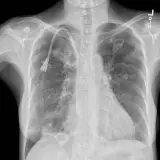

Over 2,100 interactive radiology cases, curated by radiologists for your level of training. Scroll, window, and view cases full screen — just like on PACS. Click linked findings in each writeup to jump straight to them on the image. Cases include sample reports, a focused discussion section, original illustrations, and videos.

Casos totalmente interativos com as ferramentas que você espera em um PACS — rolagem, ajuste de janela, zoom, movimentação, medidas, ROIs e modo de tela cheia.

Anotações detalhadas destacam os achados principais diretamente nos casos. Clique nos achados vinculados nas descrições dos casos para ir ao local exato no exame.